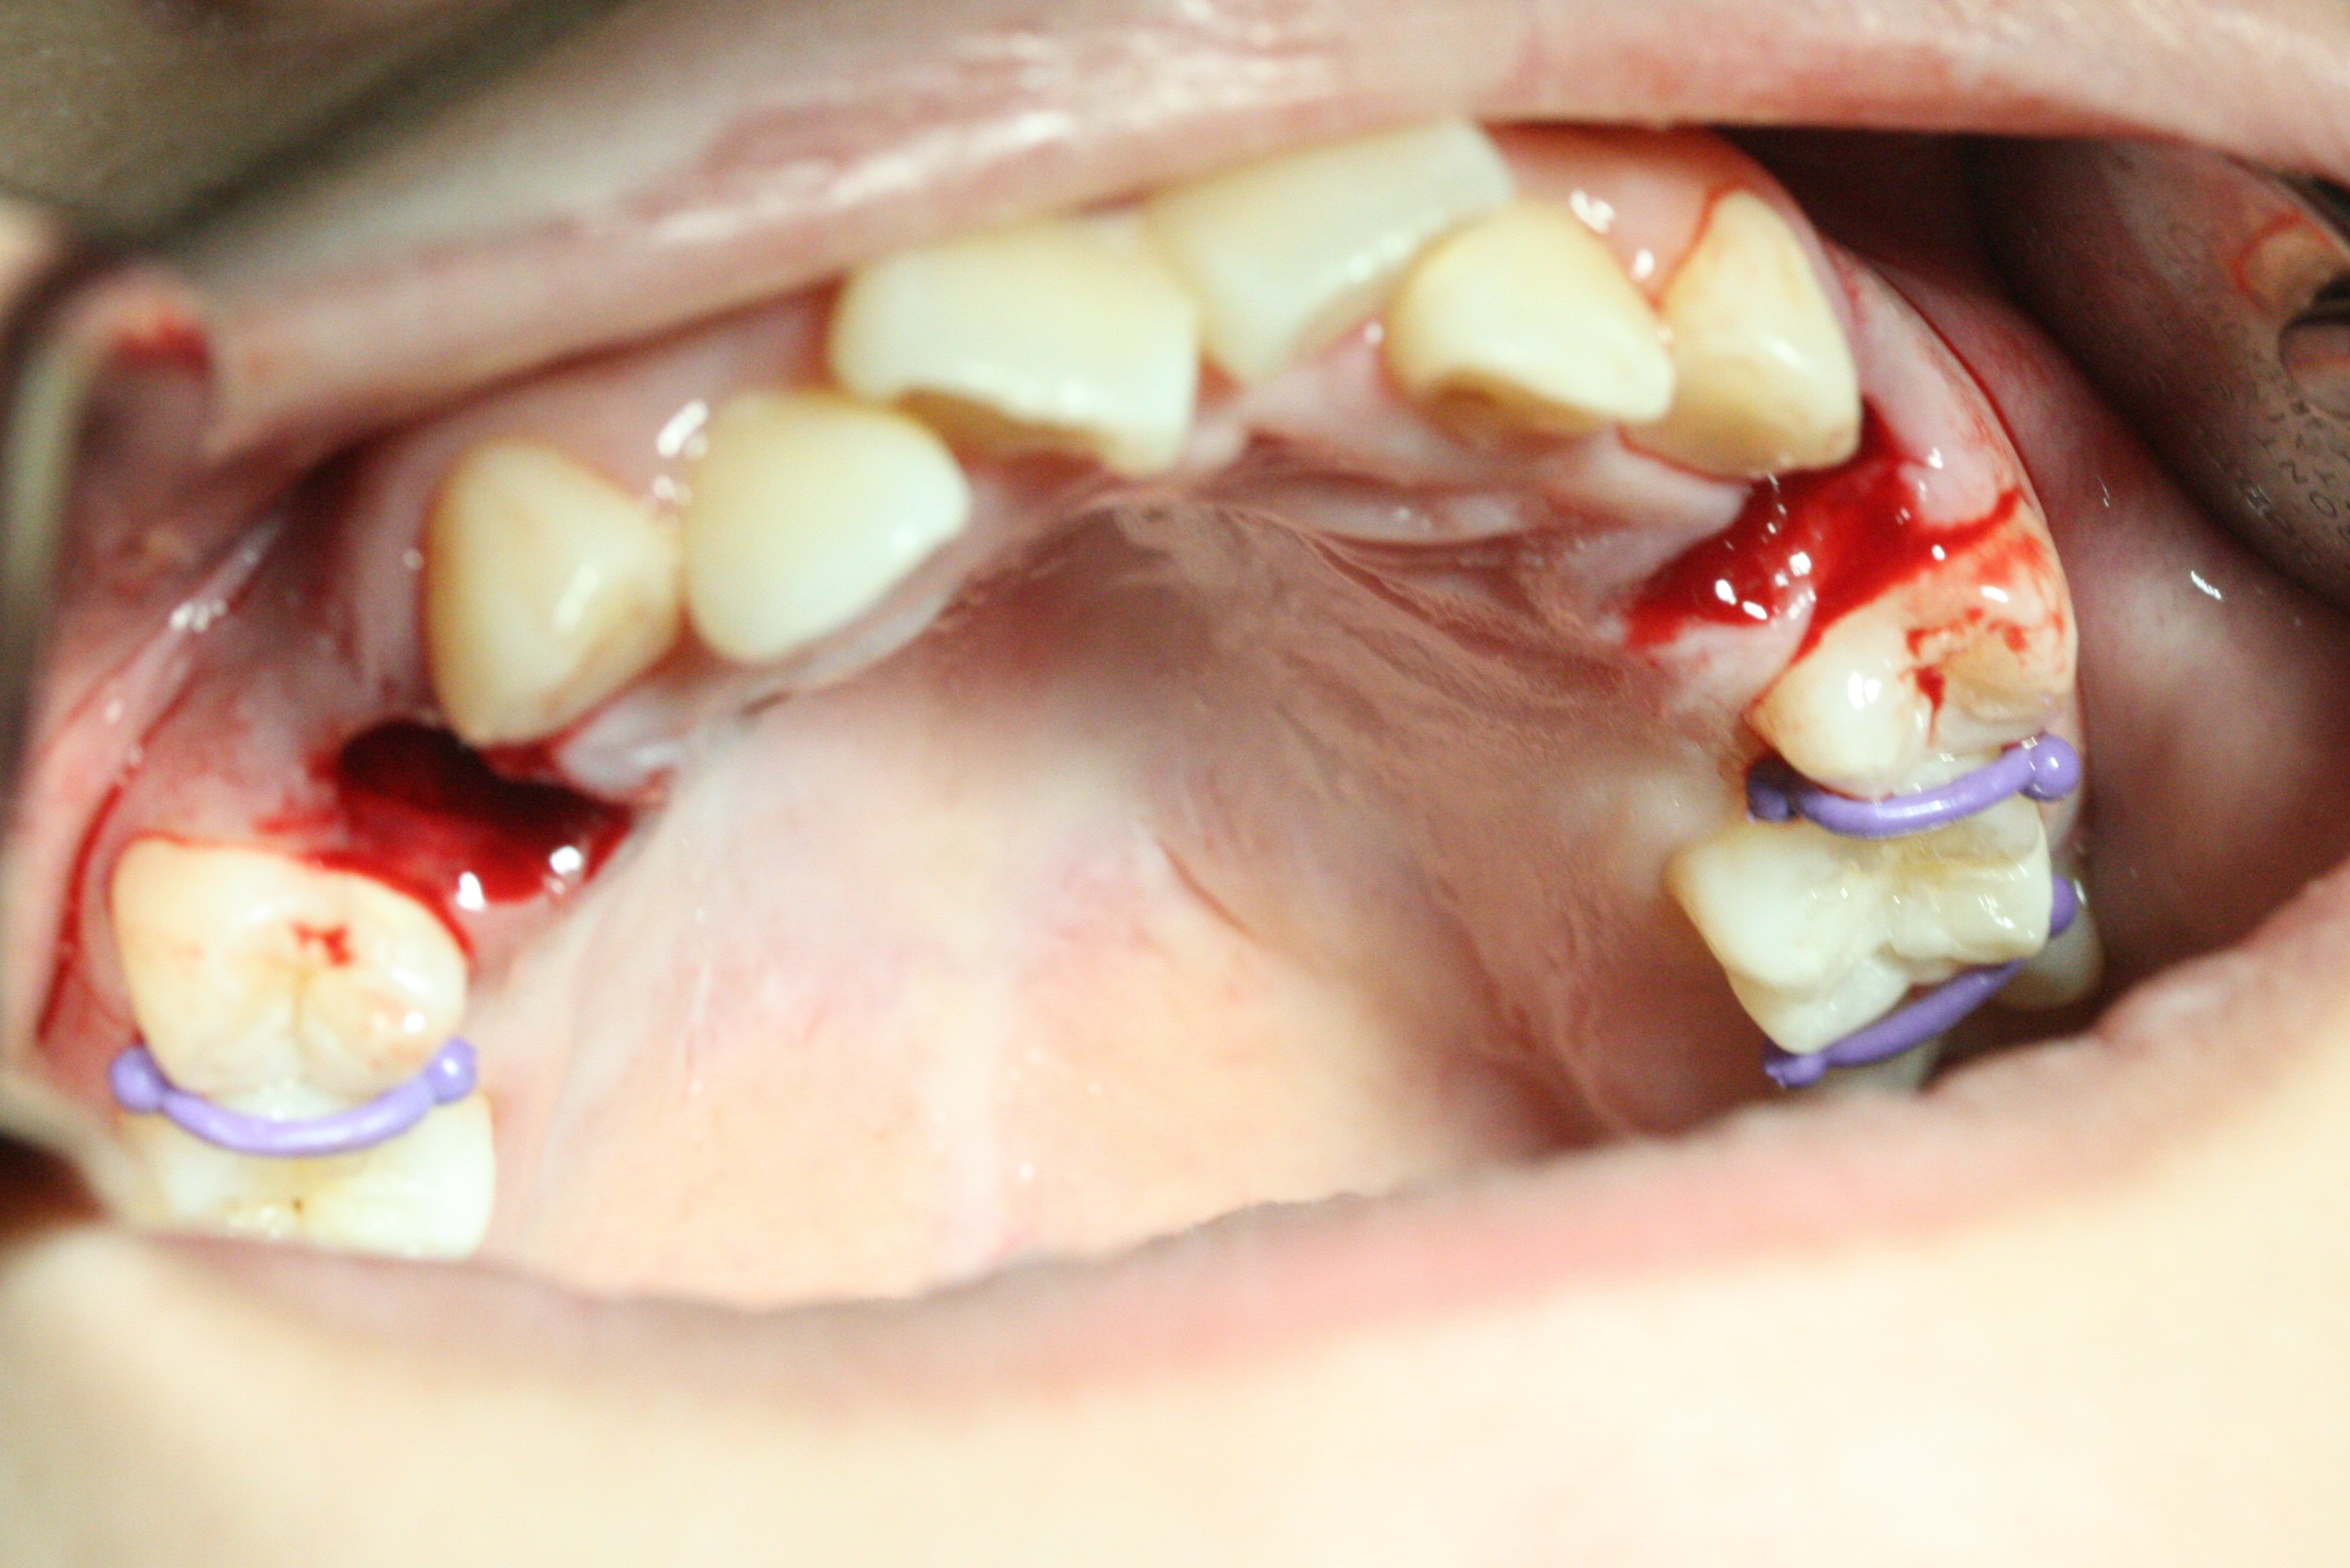

A 14-year-old woman has convex facial profile (Fig.1-4) with the upper midline shifted to the left (Fig.2). Since the roots of the 1st bicuspids are short (Fig.5), extraction should be easy. U3 will be retracted distal early with intention to correct the upper midline. With Class I occlusion at the canines and the 1st molars and good initial interdigitation (Fig.6-11), orthodontic treatment should be rewarding. Because of severe crowding (tight contact, Fig.12,13), place separators after extraction and place bands and brackets a few days later. Cephalometric analysis (Fig.14) shows that SNB is greater than SNA (82.4 vs. 81.8 degree); after extraction, retract the lower anterior teeth prior to the upper ones. It is easy to place separators after extraction (Fig.16,17).